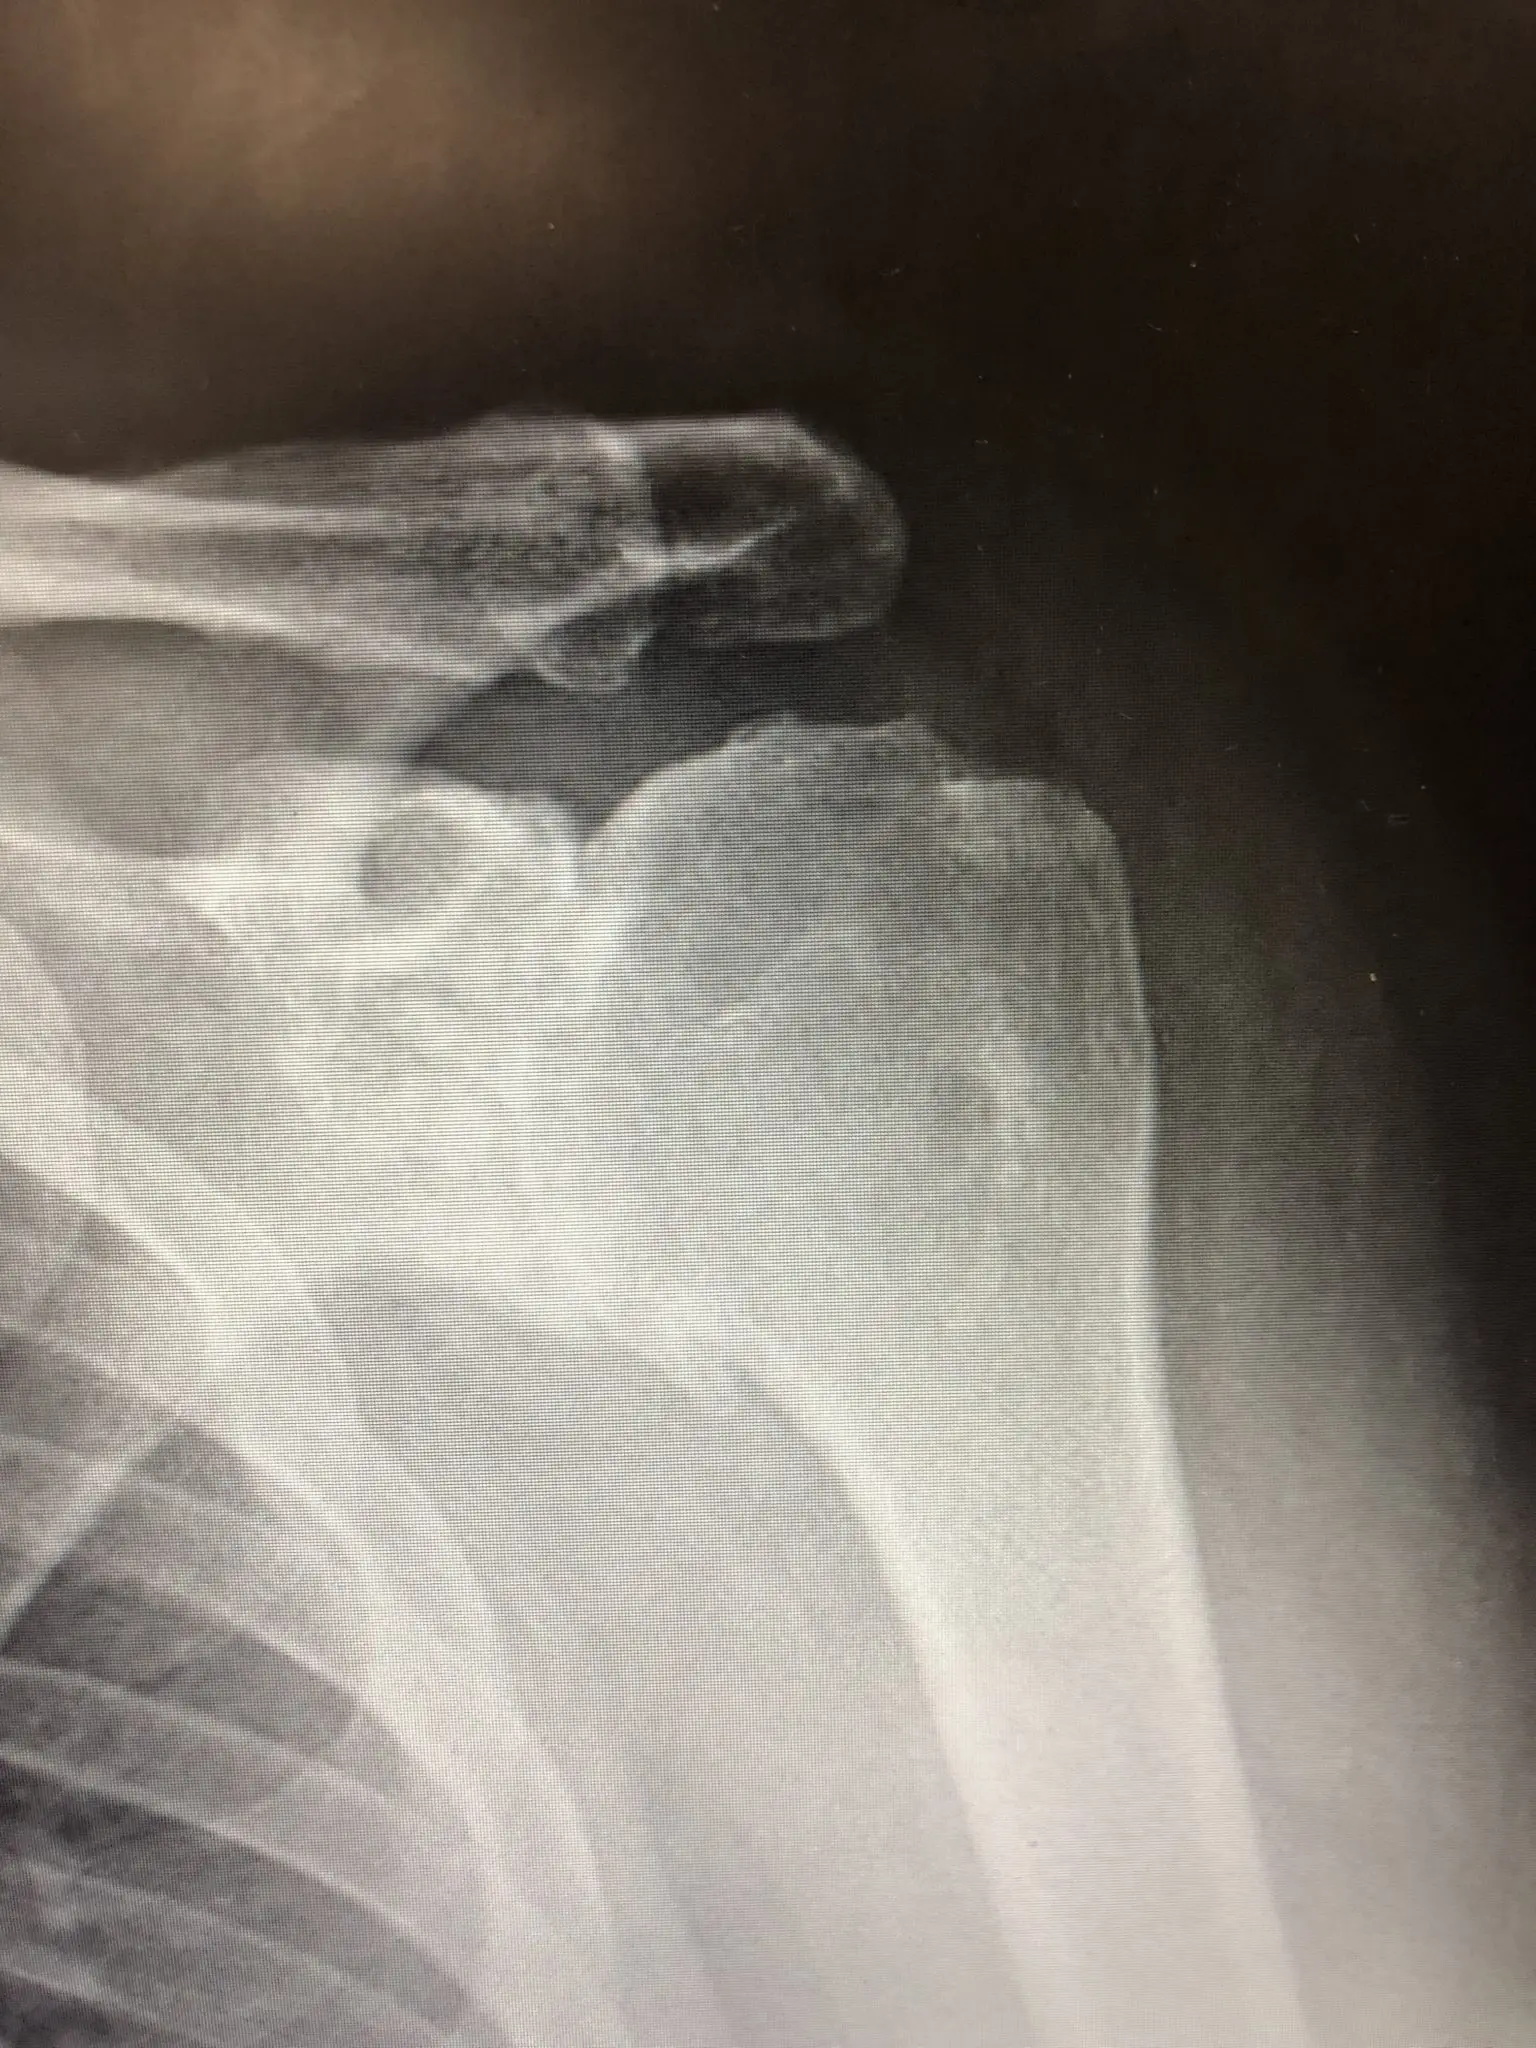

RTG - Osteoarthritis of the shoulder

Osteoarthritis of the shoulder

Osteoarthritis (arthrosis) is the most common musculoskeletal disorder. It involves the destruction of cartilage forming the joint. In people over 50, degenerative changes are usually associated with joint surface wear. The risk of developing the disease is greater if the shoulder has been regularly overloaded (e.g. in the case of manual workers), as well as in case of injuries in that area.